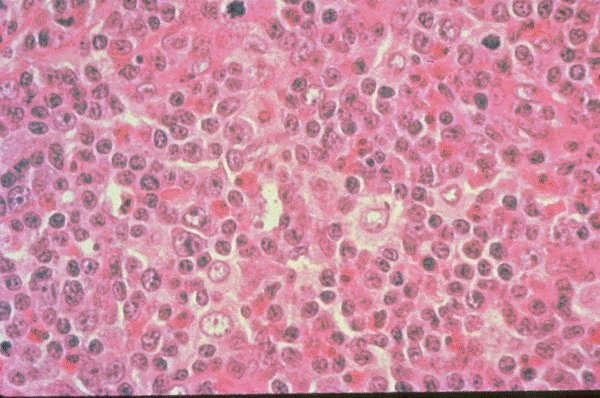

Set 4 Hematopathology of Lymph Nodes, Spleen, and Other Organs

Slide 5 of 212 Image ID 1736

Pericortical hyperplasia

This is a low power view of an H&E stained lymph

node biopsy which shows paracortical hyperplasia

in a patient who was taking dilantin. The various

types of reactive lymphocytes and other reticulo-

endothelial cells can be appreciated.